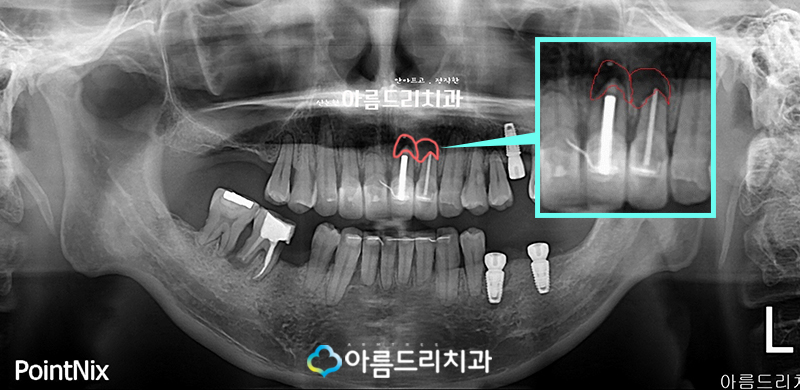

환자분의 경우 파노라마 X-ray 사진을 통해서 도 알 수 있었듯이 앞니쪽에 지속적으로 극심 한 통증이 있었으며 진단해 본 결과 사진에서 보시는 것처럼 뿌리쪽 염증으로 인한 것으로 잇몸을 절개하여 염증을 제거하게 되었습니다.

부족한 치조골(잇몸뼈)는 뼈이식을 통하여 충전하였으며 봉합만을 남겨놓고 있습니다.

그렇다면 이제 치근단절제술 후 치아의 뿌리 부분이 어떻게 변화되었는지 살펴볼께요.

왼쪽사진이 전 사진이고 오른쪽 사진이 후 사 진인데요. X-ray 상으로 볼때에도 그전에 염증 으로 인하여 검은 부분이 사라지고 정상으로 다시 돌아온 모습을 확인하실 수 있습니다.